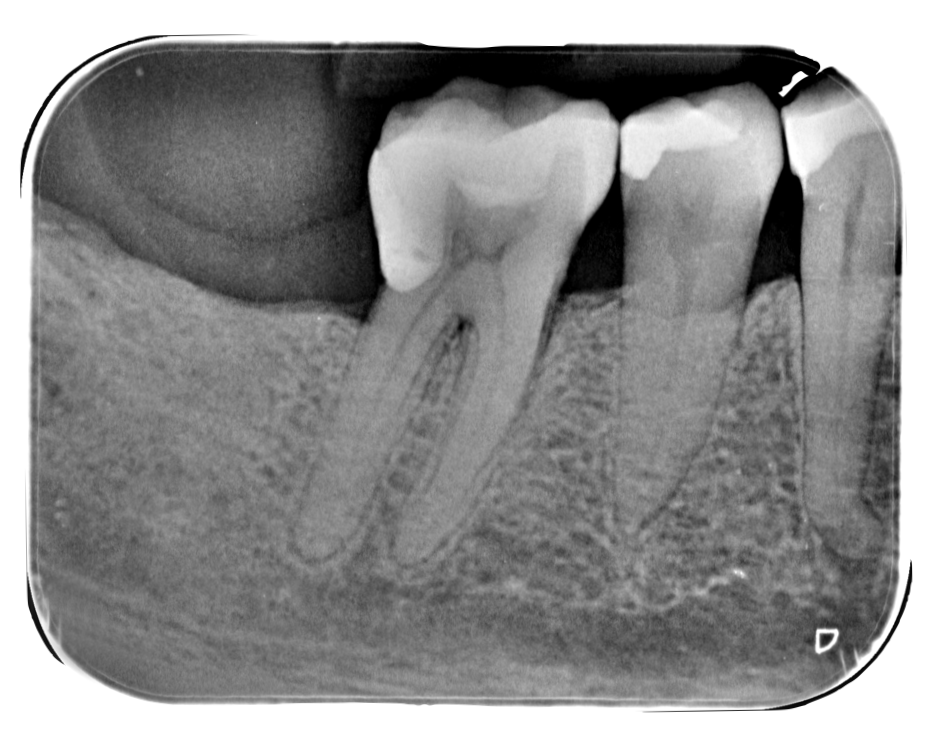

Vediamo un esempio di un caso con queste caratteristihe, un 4.6 con con necrosi pulpare  (fig.6)

Dente con canali stretti pretrattamento

Step 1: Scouting. Con uno strumento manuale k-file 06-08 si sonda la pervietà del canale e l’avanzamento progressivo fino a un k-file 10. Si rileva la prima lunghezza di lavoro con un rilevatore apicale.

Step 2: Glide Path: utilizzando lo strumento FQ Glider in modo estremamente controllato con progressione lenta andremo a creare il sentiero di scorrimento sicuro per gli strumenti di shaping in tutti i canali

Step 3: Shaping. Essendo un canale stretto in tutta la sua lunghezza, si predilige utilizzare gli strumenti FQ file 020 e 025 con conicità O4.

Una continua irrigazione del sistema canalare con Ipoclorito di Sodio al 5% è necessaria per tutta la durata del nostro trattamento.

Ricalcoliamo una seconda lunghezza di lavoro per confermare o modificare la misura precedentemente rilevata.

Step 4: Finishing. Essendo canali calcificati difficilmente il diametro apicale sarà superiore a un 0.30.

In questo caso, il dente presentava un diametro apicale di 0.25 per tutti e tre i canali (Mesio-Linguale, Mesio-Vestibolare e Distale) e non è stato necessario eseguire un Finishing meccanico.

Step 5: Irrigazione e Otturazione. Irrigazione finale abbondante con Ipoclorito di Sodio al 5% ed EDTA al 10%, meglio se attivati meccanicamente. Terminiamo con un’otturazione con tecnica single cone con coni di guttaperca dedicati di diametro 0.25 e cemento bioceramico per il sigillo tridimensionale.

Dente con canali stretti posttrattamento